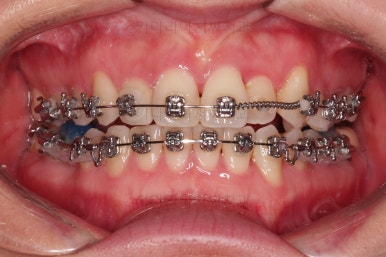

부산치과교정 키다리아저씨치과 초진 시 입안의 모습입니다.

확연히 좌우의 삐뚤어진 정도가 차이나죠.

덧니도 좌측(사진에서 보면 오른쪽) 위아래만 있는 상태고요.

좌측으로 삐뚤어져서 앞니도 좌측으로 쏠려 있는 상태였습니다.

많이 삐뚤었던 앞니도 점점 좋아지는게 보이죠.

적절하게 디테일을 손보고 마무리를 합니다.

중간중간 보철된 치아도 있고, 위아래의 중앙선까지 100% 맞기는 힘든 상황이었지만 가급적이면 매우 잘 맞춰 드렸고요.

교합이라던지 가지런한 느낌도 좋네요.